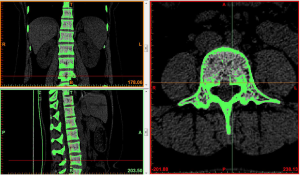

Image import: 392 horizontal images of the thoracolumbar spine in DICOM format were imported into Mimics 15.0 medical image processing software, which automatically located the images and displayed them according to the three orthogonal planes (coronal, horizontal, and sagittal), respectively (Figure 2).

Threshold segmentation: it was easy to distinguish the bones from the soft tissues based on the obvious differences in their CT values on the CT images by using the threshold segmentation method, and a mask was formed. If the gray values of adjacent pixels were close to each other and it was not easy to distinguish the boundary by the naked eye, the Draw Profile Line and the Thresholding functions in Mimics 15.0 medical image processing software were used to adjust the image threshold to 462–2,676 HU, so that the boundaries of the thoracolumbar vertebral body, intervertebral disc, sacrum, and facet joint were clearer (Figure 3).

Region growing and edit masks: the segmented regions on the above mask that were not connected to each other were formed into a new mask using region growing. The region growing feature was used to roughly extract various lumbar segments of interest. The boundary contour of each bone on each section of the scanned images was modified or erased to remove the unwanted hip bone portion, so that the boundary contour between bones could be accurately distinguished, especially the upper and lower facet joints (Figures 4,5).

At the end of the tomographic image processing, three-dimensional surface model of the spine and pelvis was reconstructed using the three-dimensional calculation function of the software to generate independent skeletal models of each vertebral body and sacrum in order to clearly and directly reproduce the three-dimensional morphology of the bone structure. The image from the three-dimensional reconstruction could be demonstrated by rotation in all directions and translation. It was also possible to hide, delete, add, and merge the components as needed in this model to obtain different looks and effects (Figure 6).